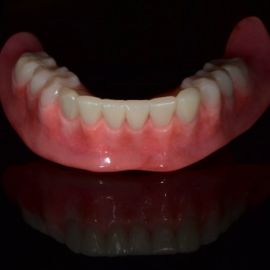

Implant dentures are a dental solution designed for those who have lost their natural teeth. They are made from high-quality materials and are crafted to mimic the natural look, feel, and function of real teeth.

Once placed, implant dentures offer benefits such as improved stability, durability, and comfort, along with restored confidence and the ability to eat and speak more naturally.